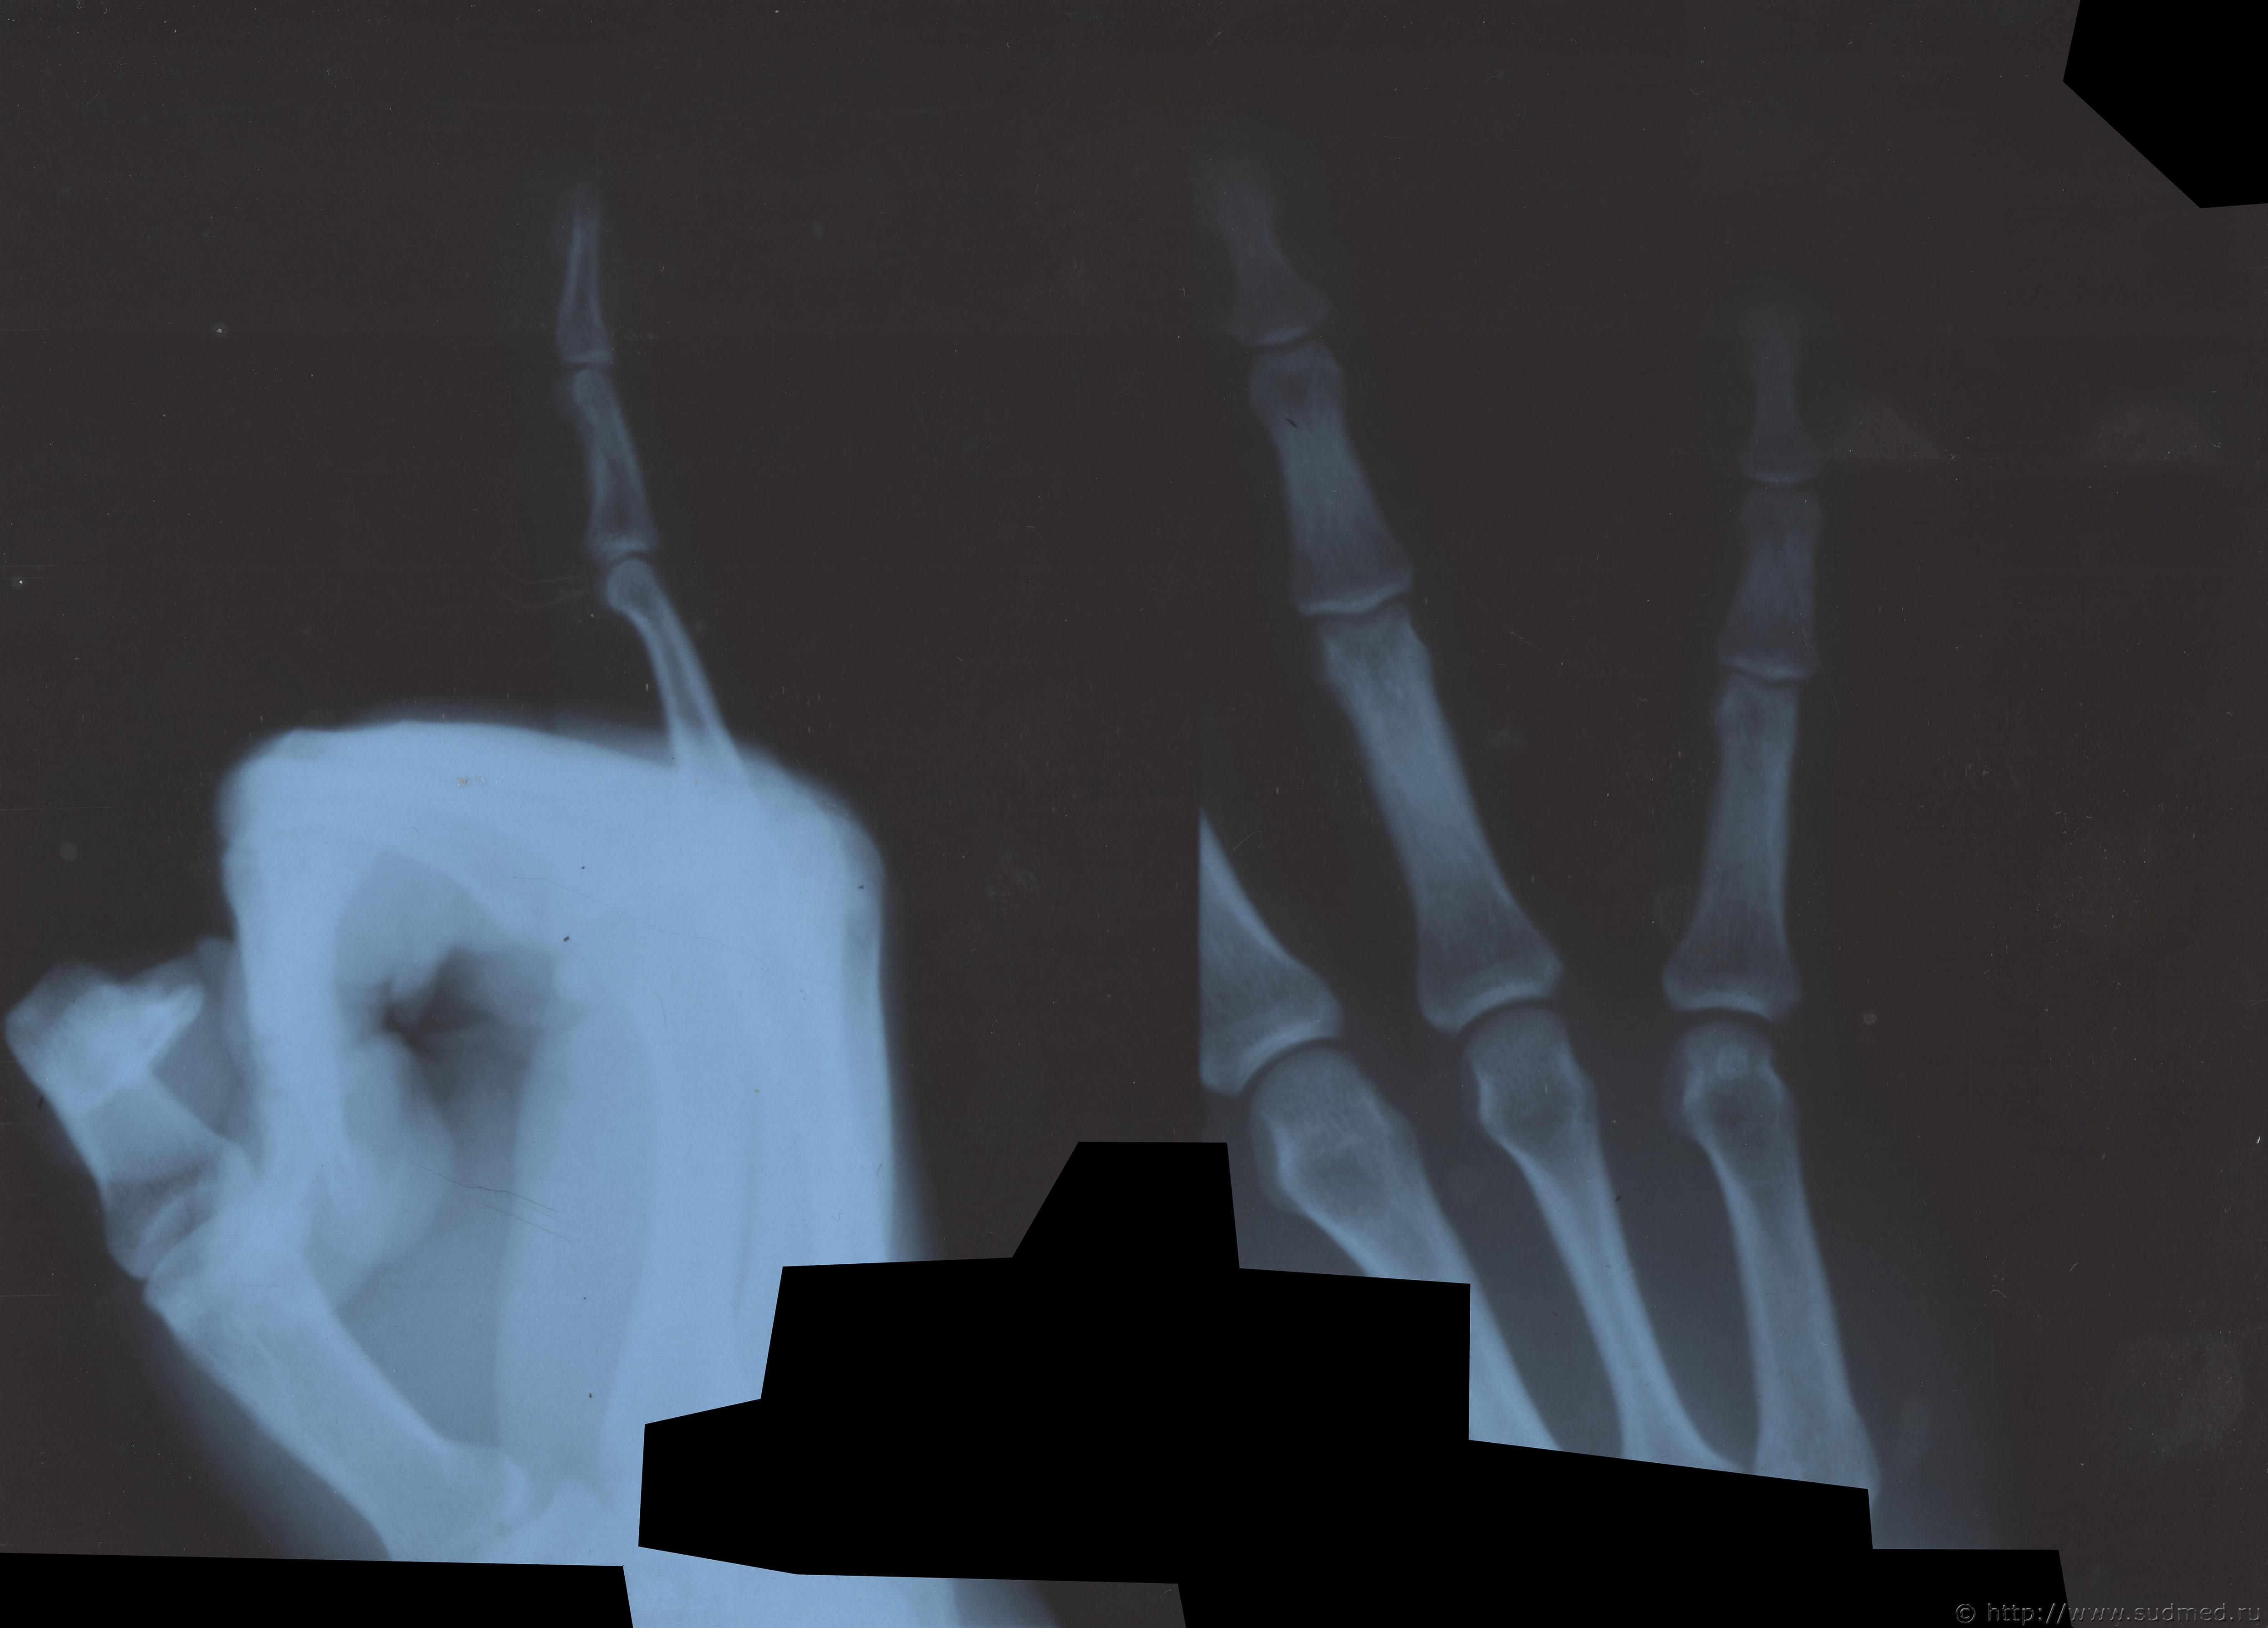

Здравствуйте. Произошла драка в которой когда я упал и меня пинали по голове, я закрыл голову рукой и нападавший попал ногой по руке. В результате он повредил мне мизинец на левой руке. Врач скорой сказала что это скорее всего ушиб. Я думал что ушиб пройдет, но палец болел и через 13 дней я обратился в травмпункт, мне сделали рентген кисти и обнаружили «З/консолидирующийся перелом о/фаланги Vп левой кисти». По этой справке мне определили средний вред здоровью. Потом когда суд мед эксперты смотрели данный снимок они не нашли перелома. Снимок сделан в травм пункте на 13 день после травмы. Можете ли вы оценить снимки. Что на них видно? Какая степень вреда здоровью?

Скорее всего технический сбой. Вот изображения в другом формате.

Достоверно перелома не видно.

Делали ли контрольные снимки?

Еще один снимок делал но там 3 месяца прошло и он на пленке. А почему достоверно перелома не видно? Травматолог и глав врач травматологии сказали что точно перелом.

В справке из травм пункта на 13 день после травмы указано:

Установлен диагноз: З/консолидирущийся перелом о/фаланги Vп левой кисти.

По поводу первого снимка, 13 дней после травмы. На диске, цифровой.

Заключение: на представленных рентгенограммах 5 пальца левой кисти от (13 дней после травмы) на электронном носителе костно-травматических изменений не выявляется.

Снимки цифровые 13 дней после травмы:

Больше вопросов и предположений вызывает не основная, а средняя фаланга. Если бы она так выглядела через 100 дней после травмы, можно было бы согласиться, что несколько месяцев назад был перелом средней фаланги. Через 13 дней перелом так выглядеть не может. Вероятно, имеется какая-то индивидуальная особенность или когда-то давно (многие месяцы-годы назад) был перелом средней фаланги мизинца. Основная фаланга особых вопросов не вызывает: согласен с рентгенологами по поводу отсутствия достоверных рентгенологических признаков перелома.